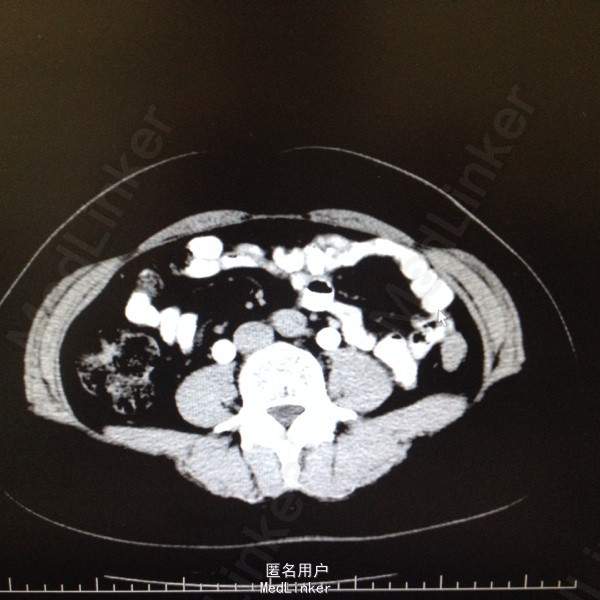

47岁女患。 病史:患者6年前因宫颈癌行全子宫及双侧附件切除。盆腔淋巴结清扫。腹主动脉旁淋巴结活检术。后又行局部放疗。因双肾积水来我科。患者自述平时轻微排尿困难,尿线细。

双肾区无叩击痛,双输尿管走形区无压痛。耻骨上区隆起,叩诊浊音。排尿后留置尿管引流尿液400ml。 辅助检查:肌酐99。 ct:双肾及输尿管积水。 留置尿管后一周泌尿系彩超:双肾积水明显减轻。具体见图片。

诊断:双肾及双输尿管积水 神经源性膀胱 给予患者留置尿管后1周行泌尿系彩超检查肾积水减轻。